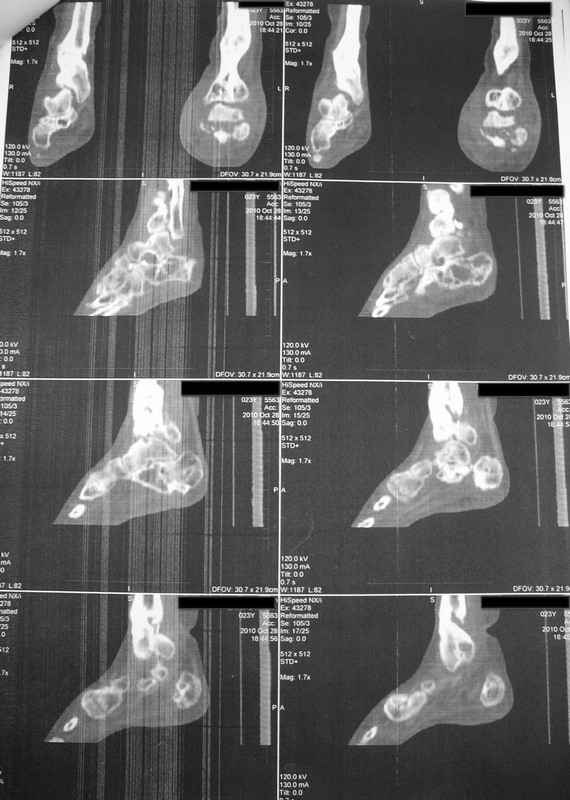

Молодая девушка со сросшимися многооскольчатыми переломами пяток и голеней.Young girl

with fractures of the calcaneus

Больная Н., 25 лет, падение с высоты (2008 г.). Жалобы на боли в области голеностопных

суставах, в области пяток при ходьбе. Лечилась в аппаратах внешней фиксации по поводу

открытых оскольчатых переломов обеих голеней, переломов пяток. Далее по поводу

несросшихся переломов голеней ЧКОС аппаратами внешней фиксации. Переломы срослись,

аппараты демонтированы весной 2010г. В левой пяточной области в месте проведения спицы

имеется сукровичное отделяемое. При ревизии гноя нет. Чем помочь девушке?

Patient N., age

25, falls from heights (2008). Complaints of pain in the ankles, in the heel when walking. She

was treated by external fixation on open comminuted fractures of both legs, fractures of the

calcaneus. Then she was treated by external fixation from nonunion of both legs. Now

fractures are fused, apparatuses removed in the spring of 2010. How to help a girl?